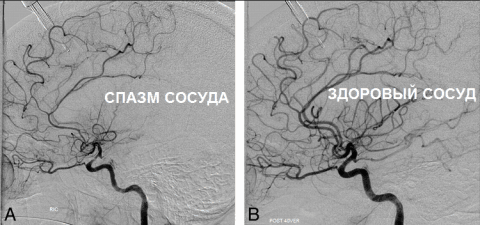

Пример здорового и больного сосуда

На фото ниже пример кровотока при спазме: